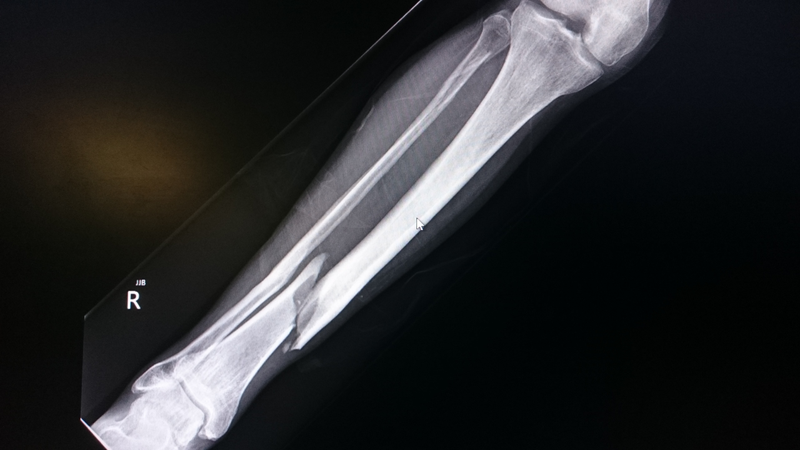

Cẳng chân gồm hai xương chính là xương chày và xương mác. Đây là vị trí dễ gãy khi trẻ bị ngã khi chạy, nhảy từ trên cao hoặc tai nạn giao thông. Đáng chú ý, khu vực này liên quan trực tiếp đến sụn tăng trưởng – vùng quyết định chiều dài của xương.

Nếu không được điều trị đúng cách, gãy xương cẳng chân có thể ảnh hưởng đến sự phát triển chiều cao hoặc làm biến dạng chi dưới. Vì vậy, trẻ cần được theo dõi sát trong suốt quá trình hồi phục.

Xương chày là xương lớn ở cẳng chân, tham gia tạo nên khớp gối và cổ chân. Gãy xương chày thường xảy ra ở thân xương và có thể điều trị bằng bó bột, nắn chỉnh hoặc sử dụng giày chỉnh hình tùy theo độ tuổi và mức độ gãy.

Việc cố định đúng giúp xương liền chắc và trẻ sớm quay lại vận động bình thường.